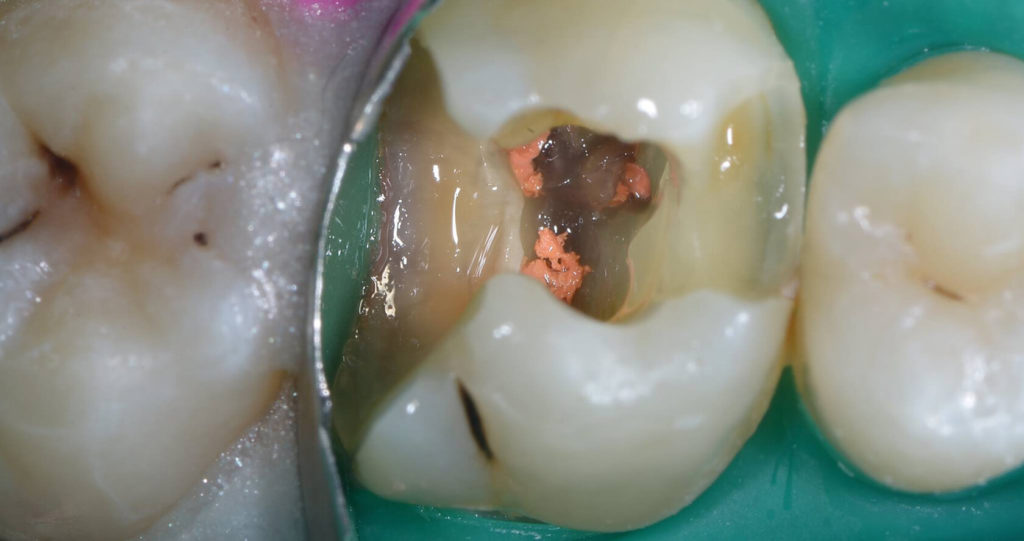

Patient presented with deep distal decay on first molar. Used deep margin elevation and papillectomy. No attempt was made to establish 3 mm biologic width space. Overlay prep and lithium disilicate indirect restoration placed. Photos from 15 month follow up included.